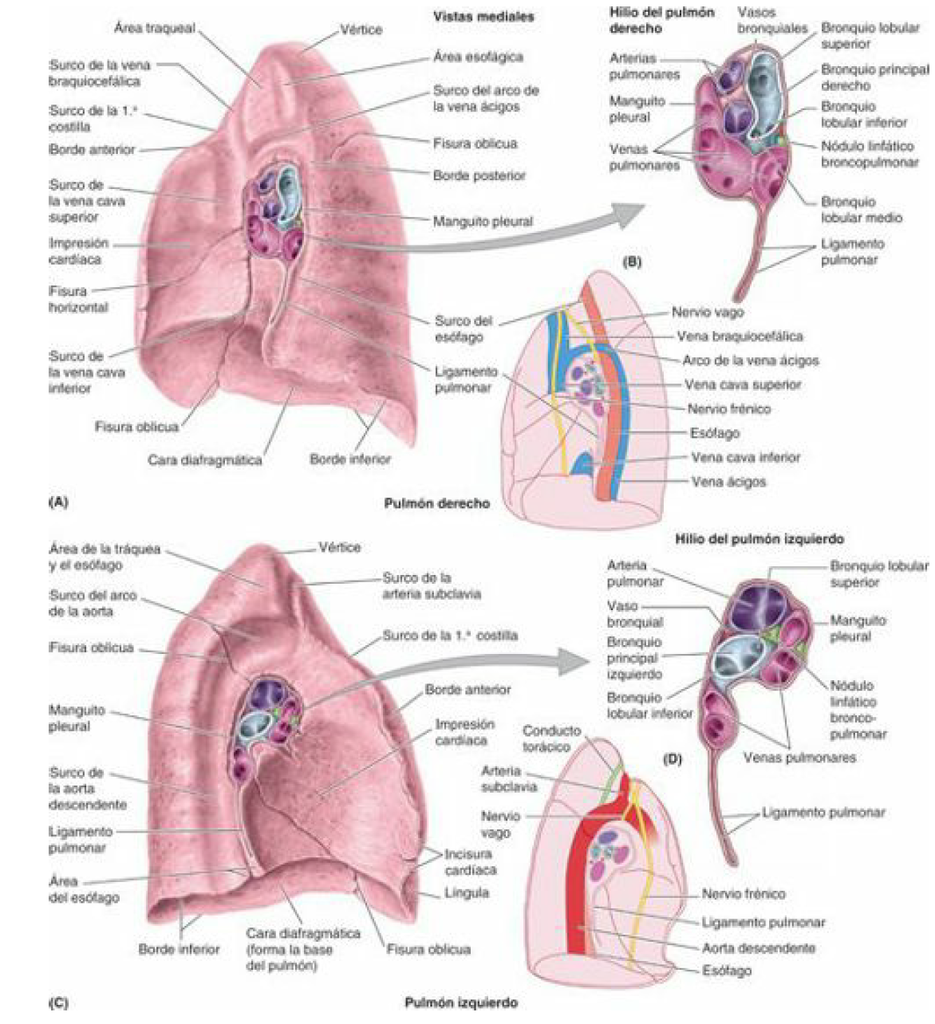

La cara mediastínica del pulmón puede mostrar impresiones dejadas por los órganos mediastínicos adyacentes, especialmente en material cadavérico fijado. Estas impresiones pueden proporcionar información importante sobre la anatomía y la relación espacial entre el pulmón y las estructuras circundantes en el mediastino.

El hilio pulmonar es una depresión anatómica de suma importancia en el pulmón, situada en la mitad inferior de su cara mediastínica, aproximadamente en la unión de los tres cuartos anteriores con el cuarto posterior de esta cara. Su circunferencia está marcada por la reflexión de la pleura visceral sobre los elementos radiculares. Esta depresión es de vital importancia en la anatomía pulmonar, ya que es el punto de entrada y salida de los principales elementos vasculares y bronquiales del pulmón.

La profundidad del hilio pulmonar puede variar dependiendo del punto de disección y la profundidad de las fisuras interlobares. La disección puede llevarse muy lejos en el pulmón, siguiendo los ejes broncovasculares, lo que revela la extensión y la complejidad de esta estructura en la anatomía pulmonar.

A nivel de la disposición morfológica, el hilio pulmonar presenta diferencias entre el lado derecho e izquierdo. A la derecha, tiene forma rectangular, con su eje mayor oblicuo hacia abajo y hacia atrás. Por otro lado, en el lado izquierdo, su forma es más redondeada, lo que ha llevado a compararlo con una raqueta, cuyo mango también está orientado hacia abajo y hacia atrás. Esta comparación también puede aplicarse al hilio derecho, lo que resalta las diferencias sutiles pero significativas entre los dos lados.

Además, tanto en el lado derecho como en el izquierdo, el hilio está prolongado hacia abajo y hacia atrás por la inserción del ligamento pulmonar de la pleura. Este ligamento, ubicado medialmente al pulmón (lóbulo inferior), se dirige medialmente hacia el esófago, lo que añade complejidad a la anatomía del hilio pulmonar y su relación con las estructuras mediastínicas adyacentes.

Comenzando con la porción retrohiliar, esta área se distingue por ser convexa y corresponder a la parte vertebral del pulmón, la cual está estrechamente relacionada con el canal costovertebral. Esta porción es notable por la impresión que deja la aorta descendente en el lado izquierdo, lo que refleja la cercanía entre el pulmón y los grandes vasos sanguíneos en esta región.

La porción prehiliar, por su parte, es predominantemente cóncava y se encuentra directamente sobre el corazón. Esta área está moldeada por la anatomía del corazón debajo de ella, y se caracteriza por la depresión débil a la derecha y fuerte a la izquierda, conocida como la impresión cardíaca. Esta diferencia en la profundidad de la depresión refleja la ubicación relativa del corazón y el pulmón en el tórax.

Finalmente, la porción suprahiliar se extiende desde el borde superior del hilio hasta el vértice del pulmón. Esta región presenta una pendiente suave y se estrecha gradualmente hacia el vértice. Aquí, se pueden observar varias impresiones importantes de estructuras vasculares, como la vena cava superior y el arco de la vena ácigos a la derecha, así como la parte terminal del arco aórtico a la izquierda. Estas impresiones son evidencia de la estrecha relación entre el pulmón y los grandes vasos sanguíneos que atraviesan la cavidad torácica, así como la importancia de esta porción en términos de anatomía vascular.